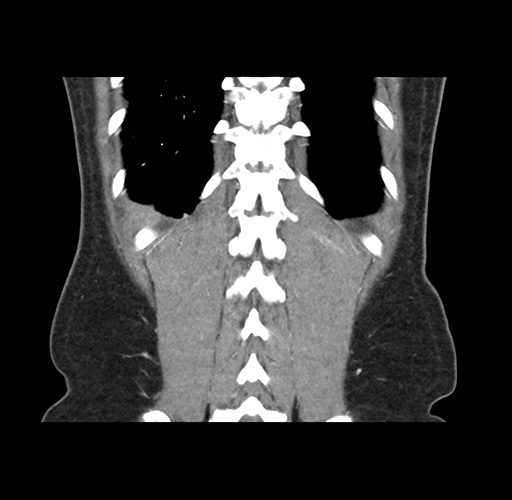

Imaging Analysis

Look through the patient's CT scan to identify any areas of concern for the necessary procedure.

Based on your CT findings, which issue(s) would give reason for "planned slowing down moment(s)" in this case?

Considering a standard left lateral sectionectomy procedure, what step(s) of the operation would you do differently in this case ?